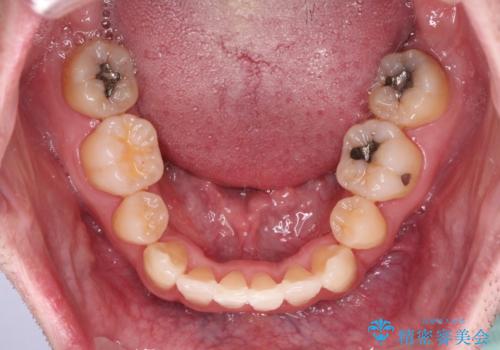

ものが挟まる 著しい叢生を解消 ワイヤー装置による抜歯矯正

叢生の解消とともに、前方に張り出した上顎前歯を引っ込めることを目的とし、上下左右の第一小臼歯4歯を抜歯をしてワイヤー矯正により治療することとしました。

治療開始直後は、あっという間に歯列が整い、すぐに終わるのではないかと思われましたが、治療の後半にブラックトライアングル解消のための処置を行ったため、当初予定していた2年半ほどの期間を要することとなりました。